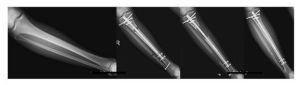

利用‘骨髓幹細胞濃縮移植法’進行的骨延長術成功

‘PRECICE內固定骨延長術’成功

‘延長後插釘術(LengtheningAndThenNailing)手術法’成功